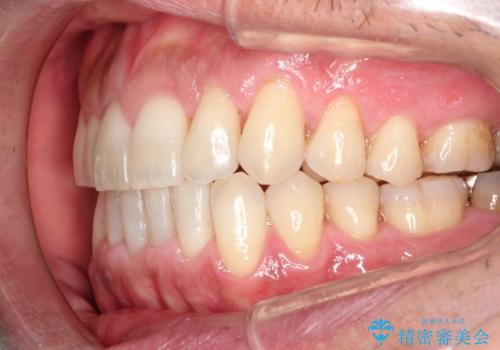

インビザライン invisalign ガタつきを治すマウスピース矯正

- 非抜歯・上顎臼歯遠心移動によるマウスピース矯正を計画した。

ガタつきを取り除くだけであれば非常に簡潔であるマウスピース矯正ですが、奥歯の位置関係の是正や、垂直的な歯の位置のコントロールなどが計画に含まれる場合、治療が難しくなってきます。